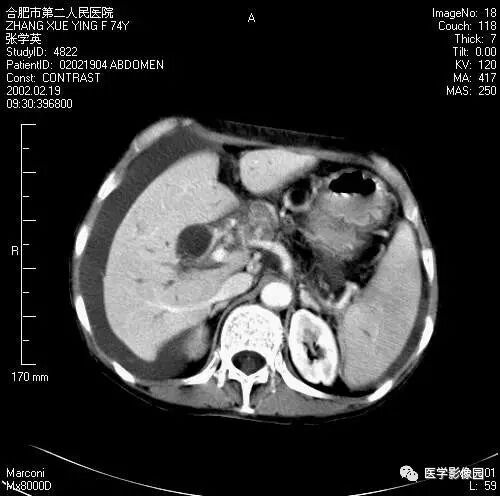

图6-4-9胰腺癌

A.CT平扫见胰头等密度肿块,

钩突明显圆隆;

B.增强扫描动脉期钩突内见境界

不清低密度灶(↑);

C.胰头部可见扩张的胆总管(↑)和

主胰管(长↑),即双管征